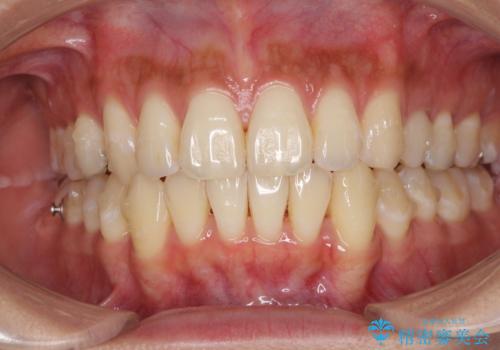

八重歯の再矯正 インビザラインでストレスなく矯正治療

- 学生の頃に矯正治療を行ったものの、保定を怠けてしまったことによる後戻りを気にして来院された患者様です。

根管治療が必要な歯があったため、矯正治療前に根管治療を行い、その後はインビザラインにより矯正治療を行うこととしました。

下顎の八重歯が上顎歯列に収まる過程で咬みにくさがありましたが、最終的には、咬み合わせも安定し、きれいに歯列を整えることができました。